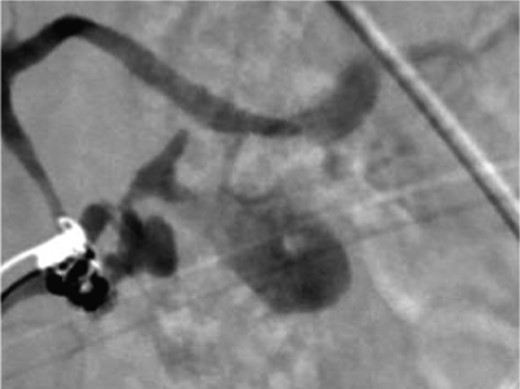

A frail 77-year-old multiparous Caucasian female with a history of aspirin and naproxen use, presented to an outside hospital with epigastric pain and an episode of hematemesis. She had no prior history of peptic ulcer disease, alcoholism or pancreatitis. The patient was hemodynamically stable with an acute anemia (hemoglobin of 7.7 g/dl), which prompted transfusion of 2 units of PRBC and transfer to a tertiary care facility. Upon transfer, she underwent an emergent upper endoscopy, which revealed a large amount of blood with clots in the lumen of the stomach. However, sufficient suctioning of the large intra-gastric clots was not possible; hence, an underlying etiology was not obtainable. The patient subsequently underwent a diagnostic angiography, which revealed a 4 cm mid-SA pseudoaneurysm with active contrast extravasation into the stomach which can be seen in Figs 1 and 2. The radiologist decided to perform a transcatheter arterial coil embolization of the artery to halt the active bleeding. A post procedure angiography revealed no further contrast extravasation. A planned upper endoscopy was repeated the following day that revealed some residual clotted blood in the stomach, no active bleeding and a deep 4 cm gastric ulcer. Due to the high risk of re-bleeding, the patient was optimized physiologically and consented and prepared for exploration. Intraoperatively we observed that the SA pseudoaneurysm was densely adherent to the posterior wall of the stomach, and coursing through an inflamed distal pancreas. We decided to proceed with an en bloc resection of SA pseudoaneurysm, distal pancreatectomy, partial gastrectomy and splenectomy. After the celiac axis was surgically defined, proximal and distal SA controls were obtained and a circumferential posterior gastrotomy was made. There was a visible posterior gastric mucosa to splenic arterial fistula, with the radiologically inserted embolic coils clearly visible. This can be seen in surgical specimen (Figs 3 and 4). Once the stomach was reflected, the splenic vessels and the pancreas were divided and the specimen removed. The pathology reports indicated active gastritis with transmural ulceration into the splenic artery (SA) and adjacent pancreatic tissue. No malignant cells were identified in the gastric or pancreatic tissue and the SA was not aneurysmal (Fig. 5). During the postoperative period, the patient had an uncomplicated recovery and was discharged on day 5.

Surgical specimen of en bloc partial gastrectomy, distal pancreatectomy and splenectomy.

Surgical specimen of en bloc partial gastrectomy, distal pancreatectomy and splenectomy. Embolic coils visible in arterial lumen.

Pathologic specimen–Gastro–splenic artery fistula. Normal caliber splenic artery.